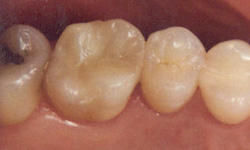

Before

After